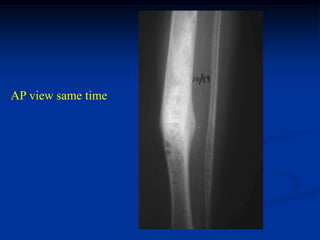

AP view same time

3.5 years later showing

good healing and no

progression of disease